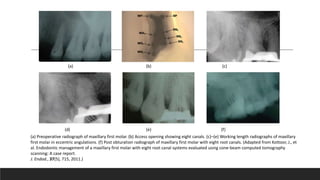

Maxillary molar with three mesiobuccal canals.

(a) Preoperative radiograph of maxillary first molar. (b) Access opening showing eight canals. (c)–(e) Working length radiographs of maxillary

first molar in eccentric angulations. (f) Post obturation radiograph of maxillary first molar with eight root canals. (Adapted from Kottoor, J., et

al. Endodontic management of a maxillary first molar with eight root canal systems evaluated using cone-beam computed tomography

scanning: A case report.

J. Endod., 37(5), 715, 2011.)